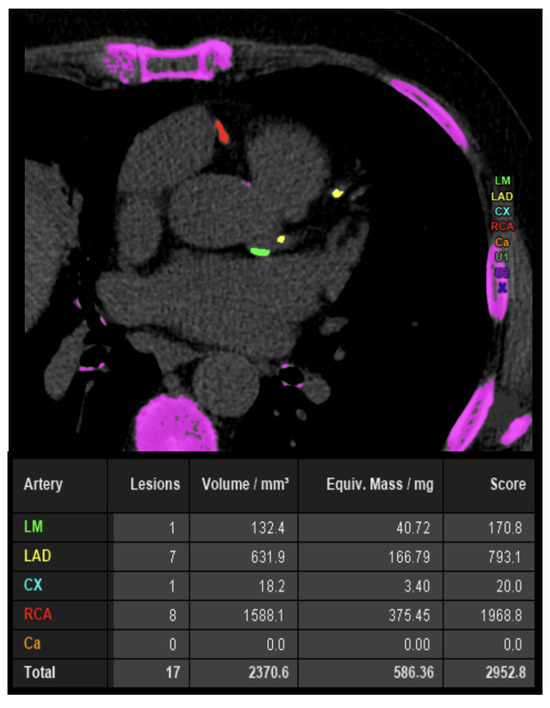

7. Coronary Artery Calcium Score